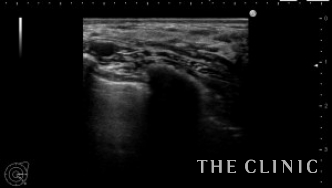

除去したヒアルロン酸です。

白く濁っています。